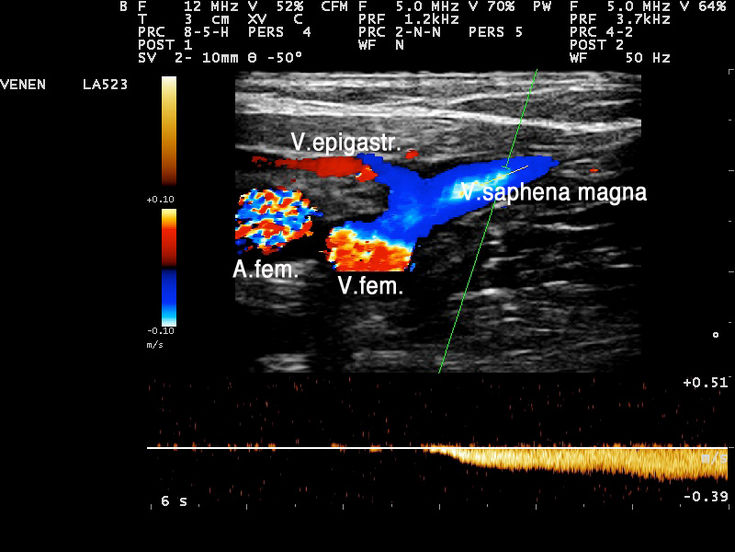

Normale Funktion der Mündungsklappe an der Einmündung der Vena saphena magna in die Vena femoralis